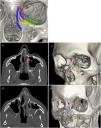

The facial skeleton is made up of four unpaired bones (frontal, ethmoid, vomer and mandible) and five paired bones (zygomatic, maxilla, nasal, lacrimal and palatine), which form a bony protective frame over the structures of the orbit, paranasal sinuses and nasal and buccal cavities. Behind them and supporting this frame, is the vitally important sphenoid bone, with the pterygoid processes on its internal surface. There are some systems that divide the facial skeleton into three parts, the upper third, consisting of the frontal bone, the lower third, corresponding to the mandible, and between them the middle third which extends from the orbital rim to the alveolar process of the maxilla15 (Fig. 1).

3D reconstruction images. (A) Division of the facial skeleton into thirds. Frontal (F), zygomatic (Z), sphenoid (S), ethmoid (E), lacrimal (L), nasal (N), upper maxilla (MX) and vomer (V). The upper third corresponds to the frontal bone. The middle third, to the bones located between the line passing through the superior orbital rim and the frontozygomatic, frontomaxillary and frontonasal sutures and the line along the alveolar process of the upper maxilla (red lines). The lower third corresponds to the mandible. (B and C) Maxillofacial buttresses. Vertical: medial maxillary (M MX), lateral maxillary (L MX), posterior maxillary (P MX) and posterior vertical mandibular (PV MD). Horizontal: upper transverse maxillary (UT MX), lower transverse maxillary (LT MX), upper transverse mandibular (UT MD) and lower transverse mandibular (LT MD).

In the bones of the facial skeleton, eight buttresses or pillars can be identified, where the bone is thickest and where the forces generated by trauma are distributed.13

Four of these buttresses are vertical and four are horizontal (Table 1).16 All of them have two-part names; the first part refers to the bone they are part of (maxilla or mandible) and the second to the surface of said bone on which they are found, with different terms for vertical (medial, lateral and posterior) and horizontal (superior and inferior) buttresses.